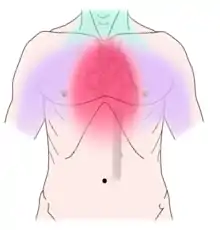

Angina pectoris can be quite painful, but many patients with angina complain of chest discomfort rather than actual pain: the discomfort is usually described as a pressure, heaviness, tightness, squeezing, burning, or choking sensation. Apart from chest discomfort, anginal pains may also be experienced in the epigastrium (upper central abdomen), back, neck area, jaw, or shoulders. This is explained by the concept of referred pain and is because the spinal level that receives visceral sensation from the heart simultaneously receives cutaneous sensation from parts of the skin specified by that spinal nerve's dermatome, without an ability to discriminate the two. Typical locations for referred pain are arms (often inner left arm), shoulders, and neck into the jaw. Angina is typically precipitated by exertion or emotional stress. It is exacerbated by having a full stomach and by cold temperatures. Pain may be accompanied by breathlessness, sweating, and nausea in some cases. In this case, the pulse rate and the blood pressure increases. Chest pain lasting only a few seconds is normally not angina (such as precordial catch syndrome).

- Retrosternal or left-sided, radiating to the left arm, neck, jaw, or back.